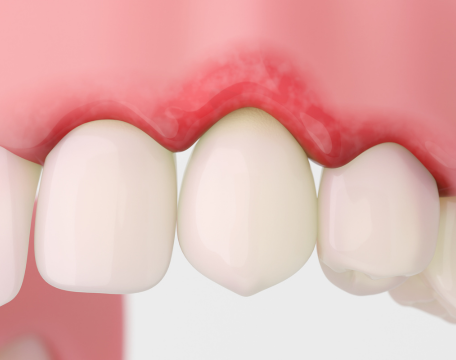

当院が最も大切にしているのは、「咬み合わせ」です。

単に虫歯を治す、歯周病をケアする、歯を白くするといった部分的な治療に留まらず、なぜその症状が起きたのか、その根本原因を探ることを重視しています。

多くの場合、その原因は「咬み合わせの不調和」にあるのです。

このバランスが崩れると、顎の痛み(顎関節症)や歯ぎしりだけでなく、肩こり、頭痛、姿勢の歪みなど、全身に様々な不調が現れることがあります。